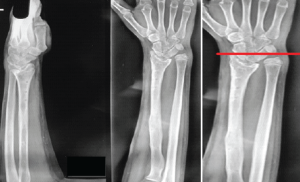

A 27-year-old female, homemaker residing in Saharanpur reported pain and tingling sensations in her right hand. We observed a spongy swelling across the wrist with signs of median nerve compression, which was transmitting a fluid impulse across the wrist joint. She had no history of tuberculosis (TB) or contact with any TB patient nor any symptoms of night sweats, weight loss, chronic cough, dyspnea, or hemoptysis. Based on the history, we made few differential diagnoss such as carpal tunnel syndrome, ganglion cyst, rheumatoid arthritis, and fungal infection. Wrist and forearm radiology revealed juxta-articular osteopenia with soft tissue swelling. She did not show any clinical manifestations of TB, but her erythrocyte sedimentation rate (ESR) level was elevated (45 mm), and the Mantoux test was positive. Upon magnetic resonance imaging (MRI), we identified a spongy soft tissue lesion compressing the median nerve over the flexor retinaculum of the right wrist (Fig. 1). Our decision was to surgically explore and excise the lesion, along with carpal tunnel release to decompress the median nerve. During surgery, we discovered a small lesion compressing the structures within the wrist, with the flexor tendon sheaths encapsulated by the mass. Careful dissection enabled us to remove the complete lesion while preserving all essential structures. During surgery, there was a singular encapsulated mass that was fully excised, followed by thorough washing and wound closure (Fig. 2).

Our patient had signs of nerve compression but there were no local signs of inflammation over the swelling, and a systemic evaluation did not reveal any tubercular foci of infection. Laboratory tests, including complete blood count, ESR, and C-reactive protein, may be either normal [11-13] or elevated [14,15]; however, these markers are non-specific for TTS, and a normal result does not exclude the diagnosis [1,12]. In extrapulmonary TB, chest X-rays are typically normal and cannot rule out TTS [1,12,15]. Radiographic findings of TTS involving the wrist may include bone erosions or cavitation, localized osteoporosis, severe destruction, and ankylosis in advanced stages [16]. These features are non-specific and can mimic inflammatory arthritis, pigmented villonodular synovitis, gout, or soft-tissue tumors [16]. Ultrasonography can help detect synovial thickening, peritendinous effusion, pus formation, and lesion extension in suspected TTS cases, but it is operator-dependent and non-specific [12]. MRI, being more sensitive and specific than ultrasound, is preferred for detecting and visualizing tubercular involvement of the synovial tendon sheaths. According to the literature, the duration of ATT for TTS ranges from 6 to 12 months when combined with surgical debridement [1,11-14]. Some authors have reported complete resolution with 12 months of ATT alone, without the need for surgical intervention [15]. ATT should be initiated as soon as the diagnosis is established, and completing the full course is crucial to prevent recurrence and the development of resistant strains [12]. The role of surgical debridement as a first-line treatment for TTS remains controversial [10,15]. Tuli suggests that surgery should be considered in patients who show resistance to 4–5 months of ATT [10]. Other indications for surgical intervention include large mass lesions requiring debulking, advanced disease (Stage 2 or 3) [12], and cases causing median nerve compression [14,17]. Many authors advocate for surgical management through debulking tenosynovectomy, combined with appropriate chemotherapy and carpal tunnel release, to reduce the risk of recurrence [14,15,17].